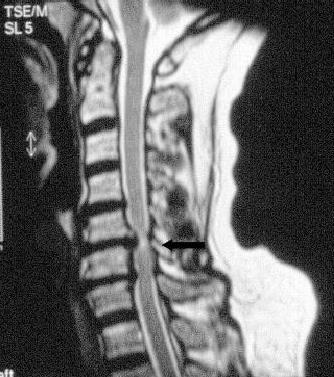

Das Gleiche gilt für Blasen-Mastdarmstörungen und Gangstörungen. Hier kann es aufgrund eines Drucks auf das Rückenmark zu bleibenden Schäden kommen. Dieses Krankheitsbild wird auch als Myelopathie beschrieben.

Durch die Untersuchung und Anamneseerhebung ergeben sich wichtige Hinweise auf die Ursachen der Beschwerden. Hieran orientiert sich auch maßgeblich die Empfehlung für oder gegen eine Operation. Ergänzend sind häufig konventionelle Röntgenaufnahmen sowie eine Kernspintomographie sinnvoll. Knochenveränderungen werden besser mit der Computertomographie erfasst. Besteht der Verdacht auf eine Rückenmarkserkrankung oder eine Störung der Nervenfunktion wird eine elektrophysiologische Untersuchung (evozierte Potentiale) organisiert. Hierbei wird, ähnlich wie bei einem Stromkabel, die Durchgängigkeit der Nervenbahnen gemessen.

Anders als an der unteren Wirbelsäule kann nur selten vom Nacken (dorsal) aus operiert werden, da das Rückenmark im Weg ist. Dieses ist nur möglich, wenn der Bandscheibenvorfall seitlich des Rückenmarks liegt. In den meisten Fällen wird jedoch von vorne (ventral) operiert.